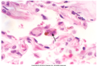

Identify types of pneumoconiosis and the compounds that initiate disease.

- What is shown in the image?

Identify types of pneumoconiosis and the compounds that initiate disease.

- What is shown in the image?

-

Asbestos bodies

- When asbestos fibers are inhaled, they become surrounded by alveolar macrophages and coated by a protein-iron complex, forming asbestos bodies.

- These bodies eventually undergo fibrosis, causing the lung tissue to become diffusely fibrotic and rigid and the airways to become distorted.

-

Asbestos bodies